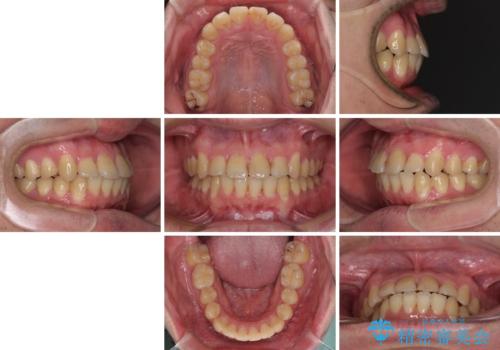

- 上下のデコボコと前歯のクロスバイトを改善したいとのことで来院された患者様です。

マウスピース矯正での自己管理には自信がないとのことで、ワイヤー装置による矯正治療を行うこととしました。

デコボコの程度は強かったのですが、口元の突出感はなかったため、非抜歯矯正としました。